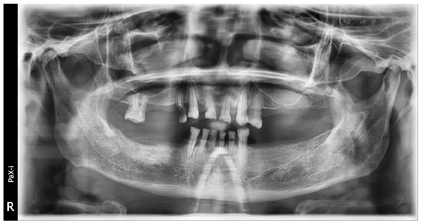

全景片及CBCT显示余留牙牙周膜间隙增宽,周围牙槽骨水平性吸收至根尖水平。临床诊断:上下颌牙列缺损;慢性牙周炎。

14、15、24-26、34-37、44-47缺失,缺牙区牙槽嵴丰满度一般;16牙探及并可穿通根分叉,但未见根分叉暴露,13残根,11近中颈部、23远中龋坏,33、43牙颈部缺损;31、41松动Ⅲ度,11、12、32、42松动Ⅱ度,16、21-23、33、43松动Ⅰ度,全口散在间隙。全口卫生状况一般,探诊深度5~8 mm,附着丧失6~9 mm,牙龈水肿,探针出血,可探及龈下结石。咬合关系欠佳,口角下垂,面下1/3高度降低,鼻唇角接近90°。上唇活动度较小,中位笑线(图1)。颞下颌关节检查无明显异常,开口型正常,开口度三横指。放射学检查:术前全景片显示13残根,16牙根尖牙槽骨吸收,11、23牙远中颈部见低密度影,余留牙牙周膜间隙增宽,周围牙槽骨水平吸收至根尖1/3-1/2(图2)。术前CBCT截图显示13牙残根,12、21、22、31、32、33、43牙颈部见不同程度楔状缺损。31、41、42牙周围牙槽骨水平吸收至根尖1/3,16、12、11、21-23、32、33、43牙牙周膜增宽,周围牙槽骨水平吸收至根尖1/2不等(图3)。